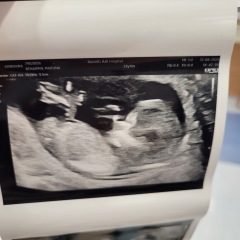

TheLemonBear · 18/05/2024 17:16

Hi had my 12 week scan yesterday, can anyone see a nub? Or predict with the skull theory?

thanks